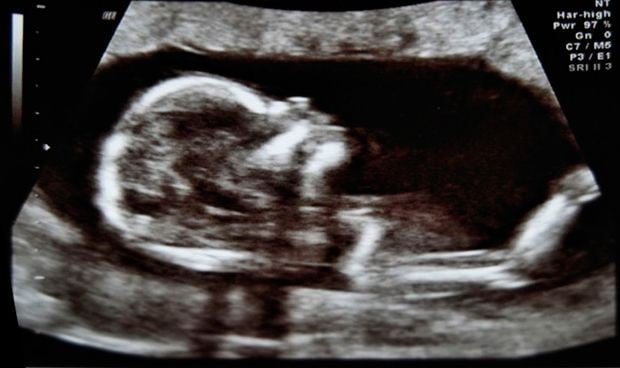

La organización fundamental de las redes cerebrales se establece en el útero durante el segundo y tercer trimestre del desarrollo fetal, según una investigación publicada en JNeurosci, la revista de la Sociedad de Neurociencias de Estados Unidos. Este hallazgo sienta las bases para comprender cómo el período prenatal da forma a la función cerebral futura.

El cerebro funciona como una red compleja de regiones que se comunican entre sí, conocida como el conectoma funcional. Durante el desarrollo fetal, el conectoma funcional comienza a tomar forma ya a finales del segundo trimestre del embarazo.

Los investigadores examinaron a 105 mujeres embarazadas entre las 20 y 40 semanas de gestación que participaron en un estudio de resonancia magnética funcional (fMRI), una tecnología no invasiva que permite a los investigadores observar las conexiones que se forman en el cerebro fetal.